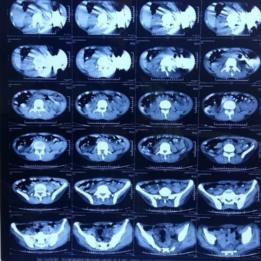

Hasil pemeriksaan CT Scan di perut pria India.